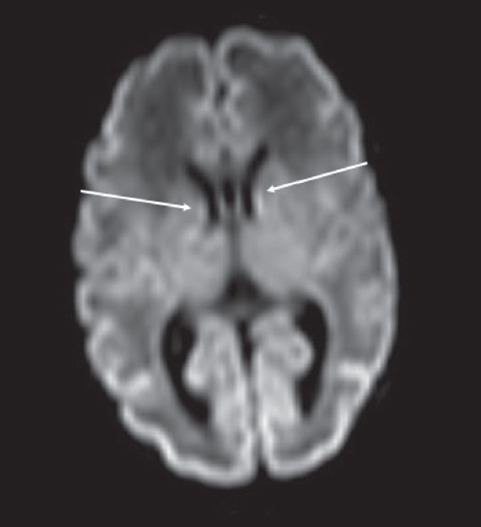

Patterns of neuroplasticity and cerebral maturation in preterm neonate can be assessed by MRI and cranial ultrasound. The score system of brain maturation includes the account of germinal matrix (GM) regression by MRI. The GM regression can be considered as pattern of neuroplasticity. There have been investigated the changes of neuroplasticity pattern or GM regression in preterm neonates with extremely low birth weight (ELBW) without intragerminal/intraventricular hemorrhages (n = 21). It is believe that the main causes of impair of GM are the intragerminal hemorrhages and hypoxia. The methods of study were cranial ultrasound (CU) and MRI. The measurement of GM was carried out by CU in anterior horn of the lateral ventricles of neonates in the study group (25-29 weeks). It was detected the GM regression in preterm neonates with increasing age, and complete GM regression to 30 week. MRI has been performed in 15 neonates from the study group on 27-38 weeks age with using the common pulse sequences – T1 WI, T2 WI and Flair. GM was detected by MRI up to 34 weeks inclusive by using the additional pulse sequence – DWI. By using common pulse sequences the GM was visualized up to 32 weeks age. Furthermore there has been pathological examination of GM in anterior horn of lateral ventricle in dead neonates from the study group (n = 3). We revealed the thickness reduction of GM in the lateral ventricles with increasing age of the dead neonates. Also we identified the delay of the GM reduction in two dead neonates 36-38 weeks age (post conceptual age) what may indicate the disorder of neuroplasticity in those preterm neonates. The performed study showed the capability of CU and MRI in examination of neuroplasticity in preterm neonates.